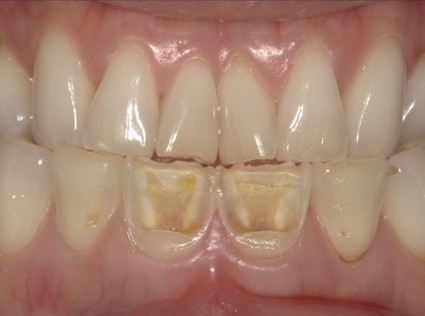

| 主訴 | 歯がしみる・見た目を改善したい |

| 状態 | 完全に神経が見えている状態だったので、根管治療を行ったのちセラミックで審美回復した症例。 |

| 料金 | 根管治療9万円+税、ファイバーコア2万円+税、仮歯1.5万円、E=MAXクラウン11.5万円+税(1本)×2本分=48万円 |

※根管治療と審美は別っていう医院が多いけど、包括的に治療できることが強み